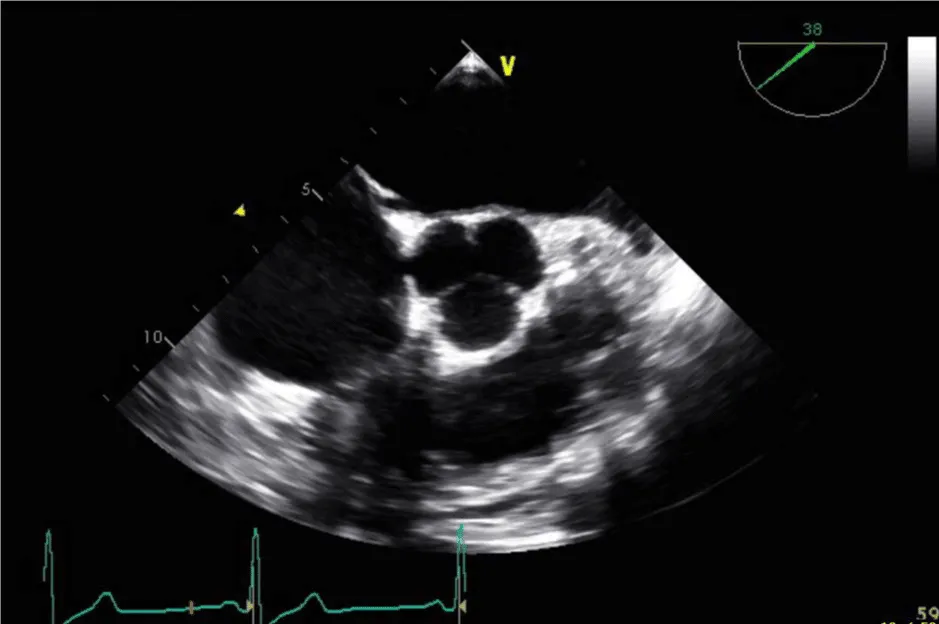

Her initial vital signs upon presentation to the hospital were; blood pressure: 161/76 mm Hg, heart rate: 96 beats per minute, respiratory rate: 27 breaths per minute. Physical exam revealed a cardiac auscultation findings of a grade 2 diastolic murmur which was loudest at the 2nd right intercostal space as well as a grade 2 systolic flow murmur. Cardiac biomarkers were elevated with initial troponin-I of 0.33 ng/mL, peak of 2.28 ng/mL and subsequent down trend. Electrocardiography (Figure 1) showed sinus rhythm with anterior and inferolateral T wave inversion and chest radiograph (Figure 2) was unremarkable. She underwent coronary angiography which revealed normal coronary arteries. The takeoff of the right coronary artery (RCA) was noted to be superior and anterior to its normal position (Figures 3A and 3B). Transthoracic and transesophageal echocardiography (TEE) revealed normal left ventricular systolic function and severe insufficiency of the aortic valve with Quadricuspid morphology (Figure 4A in Diastole, Figure 4B in Systole, Figure 4C Long Axis of the aortic valve). She underwent aortic valve replacement with a # 19mm ON-X mechanical valve. Intraoperatively it was noted that the ostium of the right coronary artery was over the aberrant leaflet. Her postoperative course was complicated by the development of supraventricular tachycardia, posteriorly localized pericardial effusion, severe hemolytic anemia, renal failure and pancreatitis leading to her death eleven days after the surgery.

Figure 4b: QAV in systole.

The diagnosis of QAV was facilitated by TEE, which revealed the characteristic findings. The short axis views of the aortic valve are optimal for making the diagnosis of QAV. The classic X shaped commissural aortic valve pattern in diastole (Figure 4B) compared to the Y shape of a trileaflet valve is diagnostic (Figure 4D) [3].